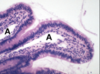

Label all:

Label all: